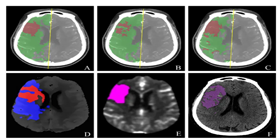

已应用于西医医疗设备医疗诊断和中医诊断,,,,为诊疗提供辅助决策支持。。